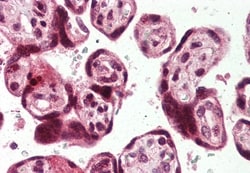

Invitrogen™ USP2 Polyclonal Antibody

Percent identity with other species by BLAST analysis: Human, Gorilla, Gibbon, Monkey, Marmoset, Mouse, Rat, Dog, Bovine, Hamster, Elephant, Panda, Horse, Rabbit, Opossum (100%); Pig (94%). Immunohistochemistry with formalin-fixed paraffin-embedded tissues requires pretreatment with Proteinase K.

| Applications | Immunohistochemistry (Paraffin) |